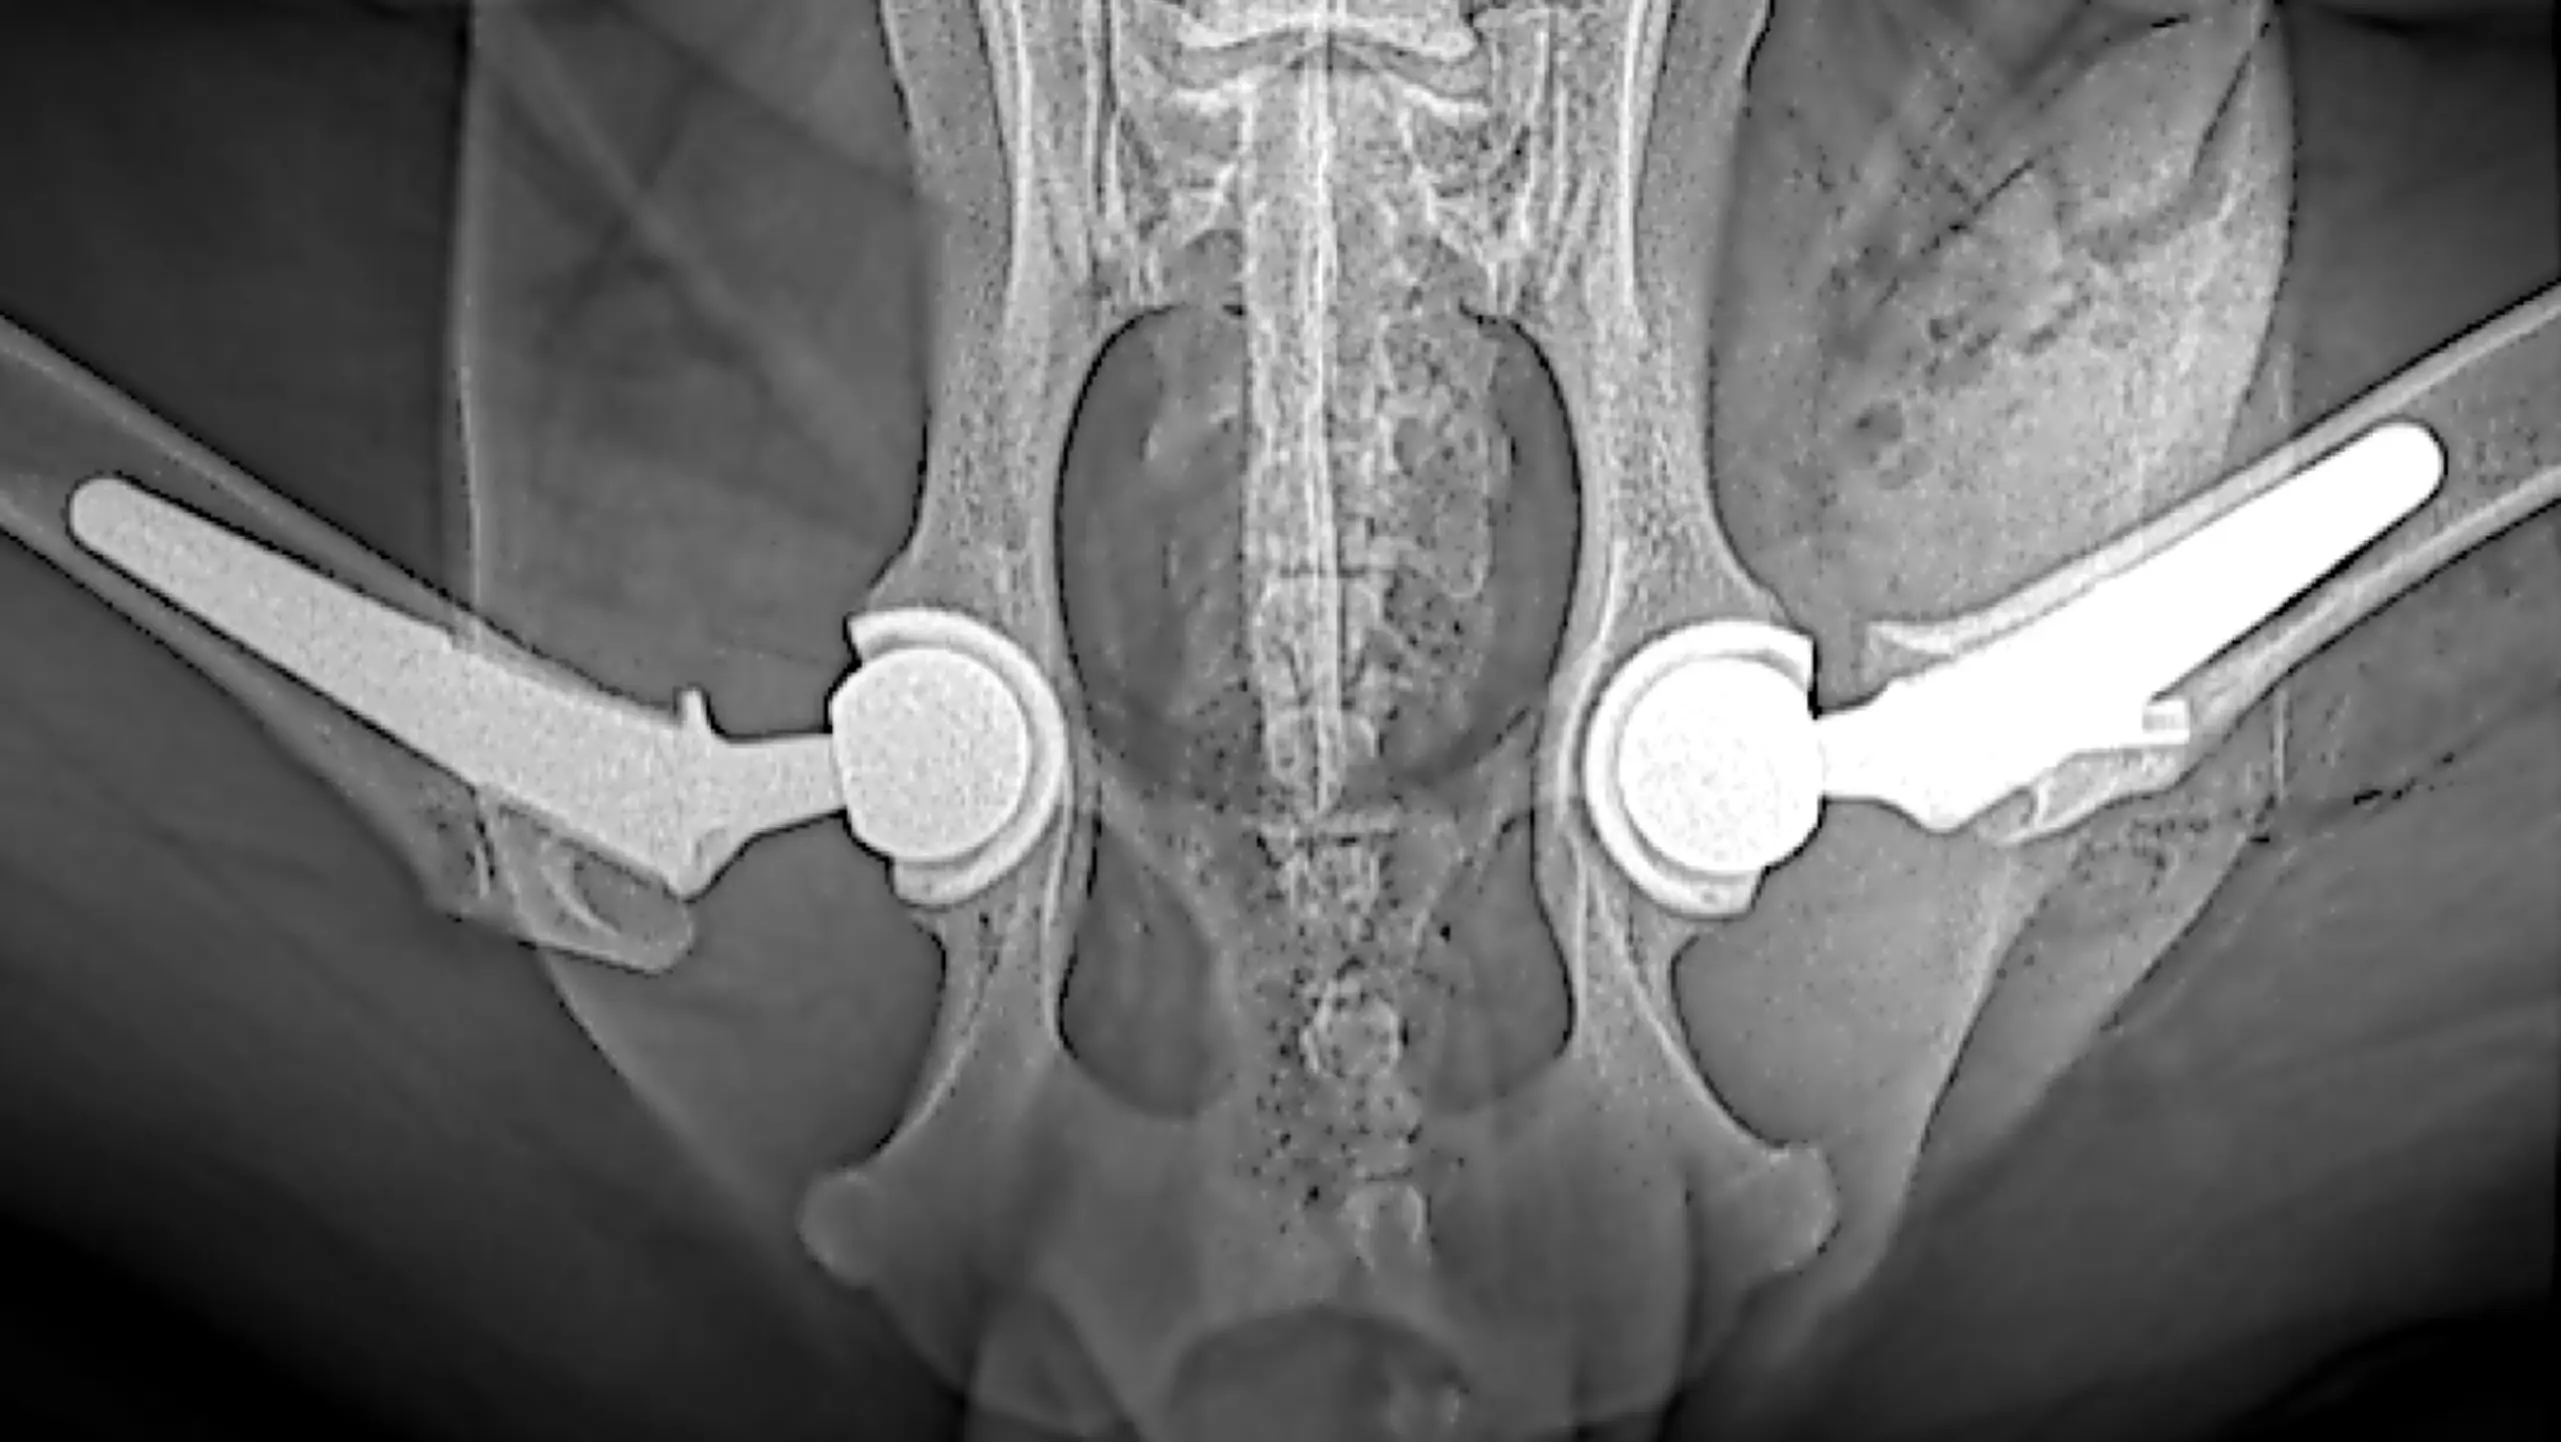

Total Hip Replacement

A CT scan allows surgeons to view bones and joints in 3 dimensions and has many advantages when compared to standard radiographs. A CT may also be used to create life-sized anatomic bone models, custom surgical guides and implants including bone plates or joint replacement components using 3-D printing technology.

3D computerized planning

means surgical precision!